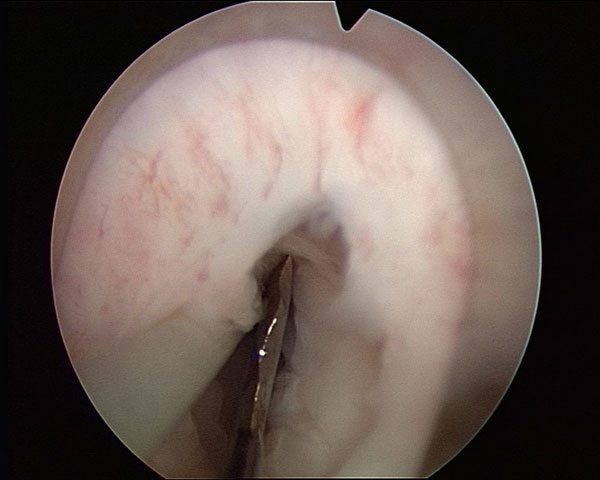

Esempio di incisione dell'uretra e preparazione dello spazio per l'innesto

Ci sono fondamentalmente 2 tecniche di "ampliamento" del tubo uretrale, ristretto dalla stenosi : si posiziona l'innesto dorsalmente (tra uretra e corpi cavernosi) o ventralmente (sotto). In pratica si incide l'uretra , si apre la stenosi e si aumenta il diametro del tratto interessato inserendocindoci l'innesto. E' certamente un intervento risolutivo, ma richiede una valutazione intraoperatoria per decidere dove mettere l'innesto e di che dimensioni deve essere. Spesso infatti le indagini preoperatorie non dicono con certezza quale sia veramente la lunghezza della stenosi. Si tratta di "chirurgia sartoriale": il chirurgo ritaglia l'intervento sul singolo paziente; è però la chirurgia che permette il miglior risultato funzionale e d estetico. Si eliminano i fastidi urinari delle stenosi , si rispettano i nervi dell' erezione e si evitano disturbi dell'eiaculazione.